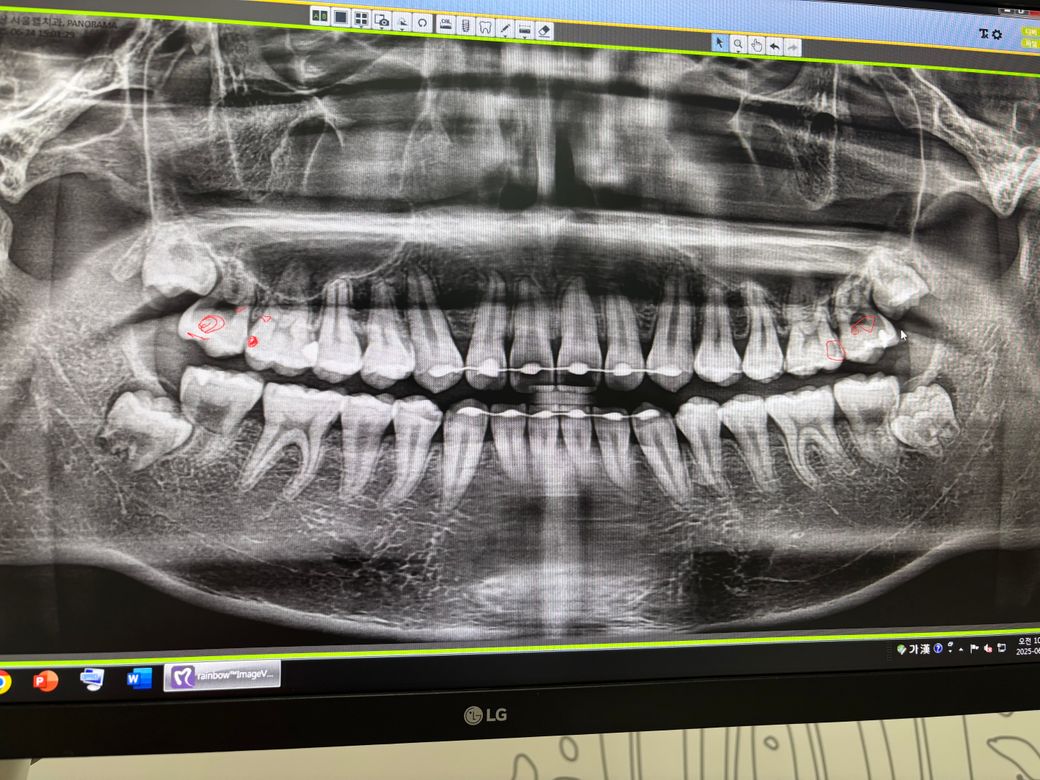

제 치아 엑스레이인데요. 치과에서는 양쪽 제1 대구치에 인접면 충치가 생겼다고 인레이 하자고 그러던데 혹시 엑스레이 상으로 이상한 부분이 또 있을까요? 제2 대구치에 검은색으로 빈공간이 유달리 크게 생겨있고 뿌리가 짧아보이는데 괜찮나요? 그리고 제 현재 사랑니는 어떤 상태인지 알려주시면 감사하겠습니다. 저 사랑니가 제대로 나올까요?

치아의 뿔기ㅏ 짧아보이긴 하지만 그렇다고해서 크게 문제가 되는건 없습니다. 치아 사이에 충치가 잇는거 같고 사랑니는 매복된 상태라 특별한 이유가 없다면 발치를 안하셔도 될것같습니다.

제2 대구치에 검은색으로 빈공간이 유달리 크게 생겨있고 뿌리가 짧아보이는데 괜찮나요? -> 네 정상입니다 괜찮습니다

사랑니는 대체로 제2대구치에 걸려있습니다. 정상맹출되기는 어려워보입니다.